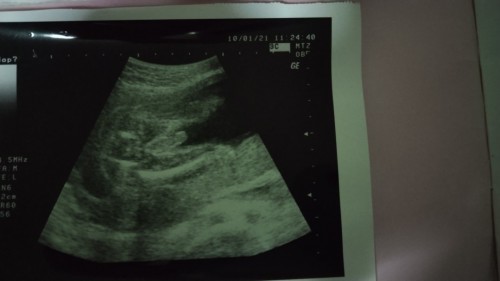

แม่ๆๆท่านไหนเป็นมั้งค่ะ เบื่ออาหาร ท้องแรกค่ะ ตอนนี้7เดือน น้องน้ำหนัก650 ต้องทำยังงัยทั้งค่ะ

หมอแจ้งว่าน้ำหนักน้องต่ำกว่าเกณฑ์ไหมคะ ถ้าเทียบกับของเรา ตอน 7 เดือน จะน้อยกว่าอยู่นะ โฟกัสที่หมอบอกว่าน้องน้ำหนักตามเกณฑ์ไหม ถ้าไม่ถึงคุณแม่ต้องอัดโปรตีนเยอะๆนะคะ (ไข่ ปลา ไก่ เนื้อ ถั่ว ประมาณนี้ ทานให้หลากหลายจะได้ไม่เอียนเบื่อ) ถ้าไม่ได้แพ้ทานแล้วอ้วกออก ถึงจะเบื่อก็ทำเพื่อน้องนะคะ สู้ๆนะแม่

เราพึ่งเข้าเดือนที่7 นน.น้อง1155แล้ว แม่ต้องบำรุงน้องเยอะๆเข้าไว้นะ แม่อาจเบื่ออาหารแต่น้องต้องการอาหารมากๆ บ้านนี้แรกๆก็เบื่อแต่ฝืนกิน วันหนึ่งกิน4-5มื้อต่อวันเลย

ตรวจล่าสุดน้อง 28+2 น้องหนัก1155 ของแม่ถือว่าน้ำหนักตกเกณฑ์มากเลย พยายามทานมื้อนึงกินสัก4-5รอบในหนึ่งวัน กินของที่มีประโยชน์กับลูกค่ะ